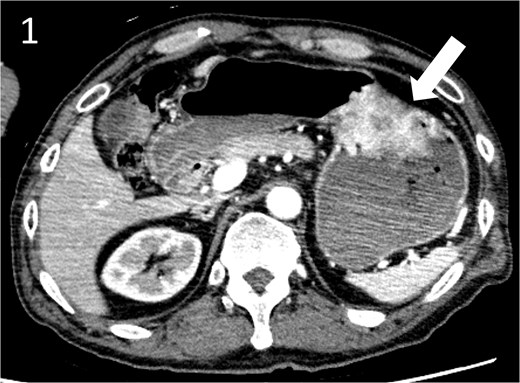

A 59-year-old man presented to the emergency department with loss of consciousness and hematemesis. His blood pressure was 90/50 mmHg. The patient’s haemoglobin level was 7.9 g/dL. The patient was haemodynamically unstable, and 12 units of red blood cell (RBC) concentrate were administered. Contrast-enhanced computed tomography (CT) revealed a gastric hyper-vascular mass on the lesser curvature (Fig. 1). Emergency upper gastrointestinal (GI) endoscopy performed under endotracheal intubation and ventilatory management revealed a large type 1 oozing tumour (Fig. 2a). Haemostatic procedures were not performed due to technical difficulties. Emergency angiography revealed a tumour stain from the left gastric artery, which was coil embolized (Fig. 3). Upper GI endoscopy 2 days later revealed no bleeding (Fig. 2b). After embolization, the patient became haemodynamically stable. It was later discovered that he had undergone open omental filling at another hospital 1 year prior due to GC perforation and left his disease untreated for a year at his own discretion. The patient received combination chemotherapy with S-1 and oxaliplatin, which was remarkably effective. Eight months after embolization, laparoscopic total gastrectomy with Roux-en-Y reconstruction and lymph node dissection were performed. The final histopathological diagnosis was T2N0M0 stage IB. Macroscopic findings revealed a type 1 tumour in the upper part of the stomach. Histopathological findings revealed that the tumour was a well-differentiated tubular adenocarcinoma. All surgical margins were negative. The patient had an uneventful postoperative course and was discharged 7 days after surgery. The patient was well, with no recurrence noted during the 35 months of follow-up.

Angiographic images; (a) the left gastric arteriography showing tumour staining (arrow); (b) the left gastric artery was coil embolized.